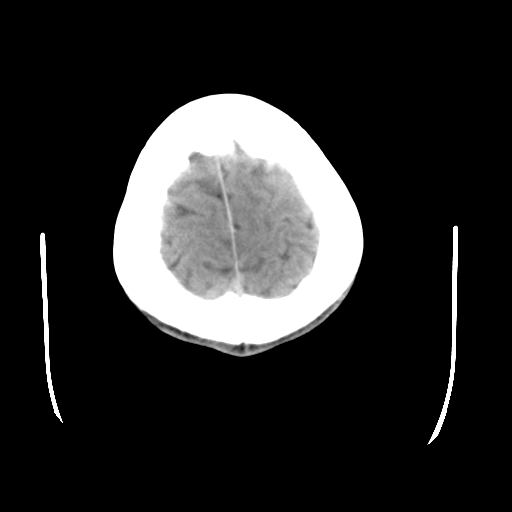

标题: CT23601:男, 17岁,剧烈头痛一小时。 [打印本页]

男, 17岁,剧烈头痛一小时。